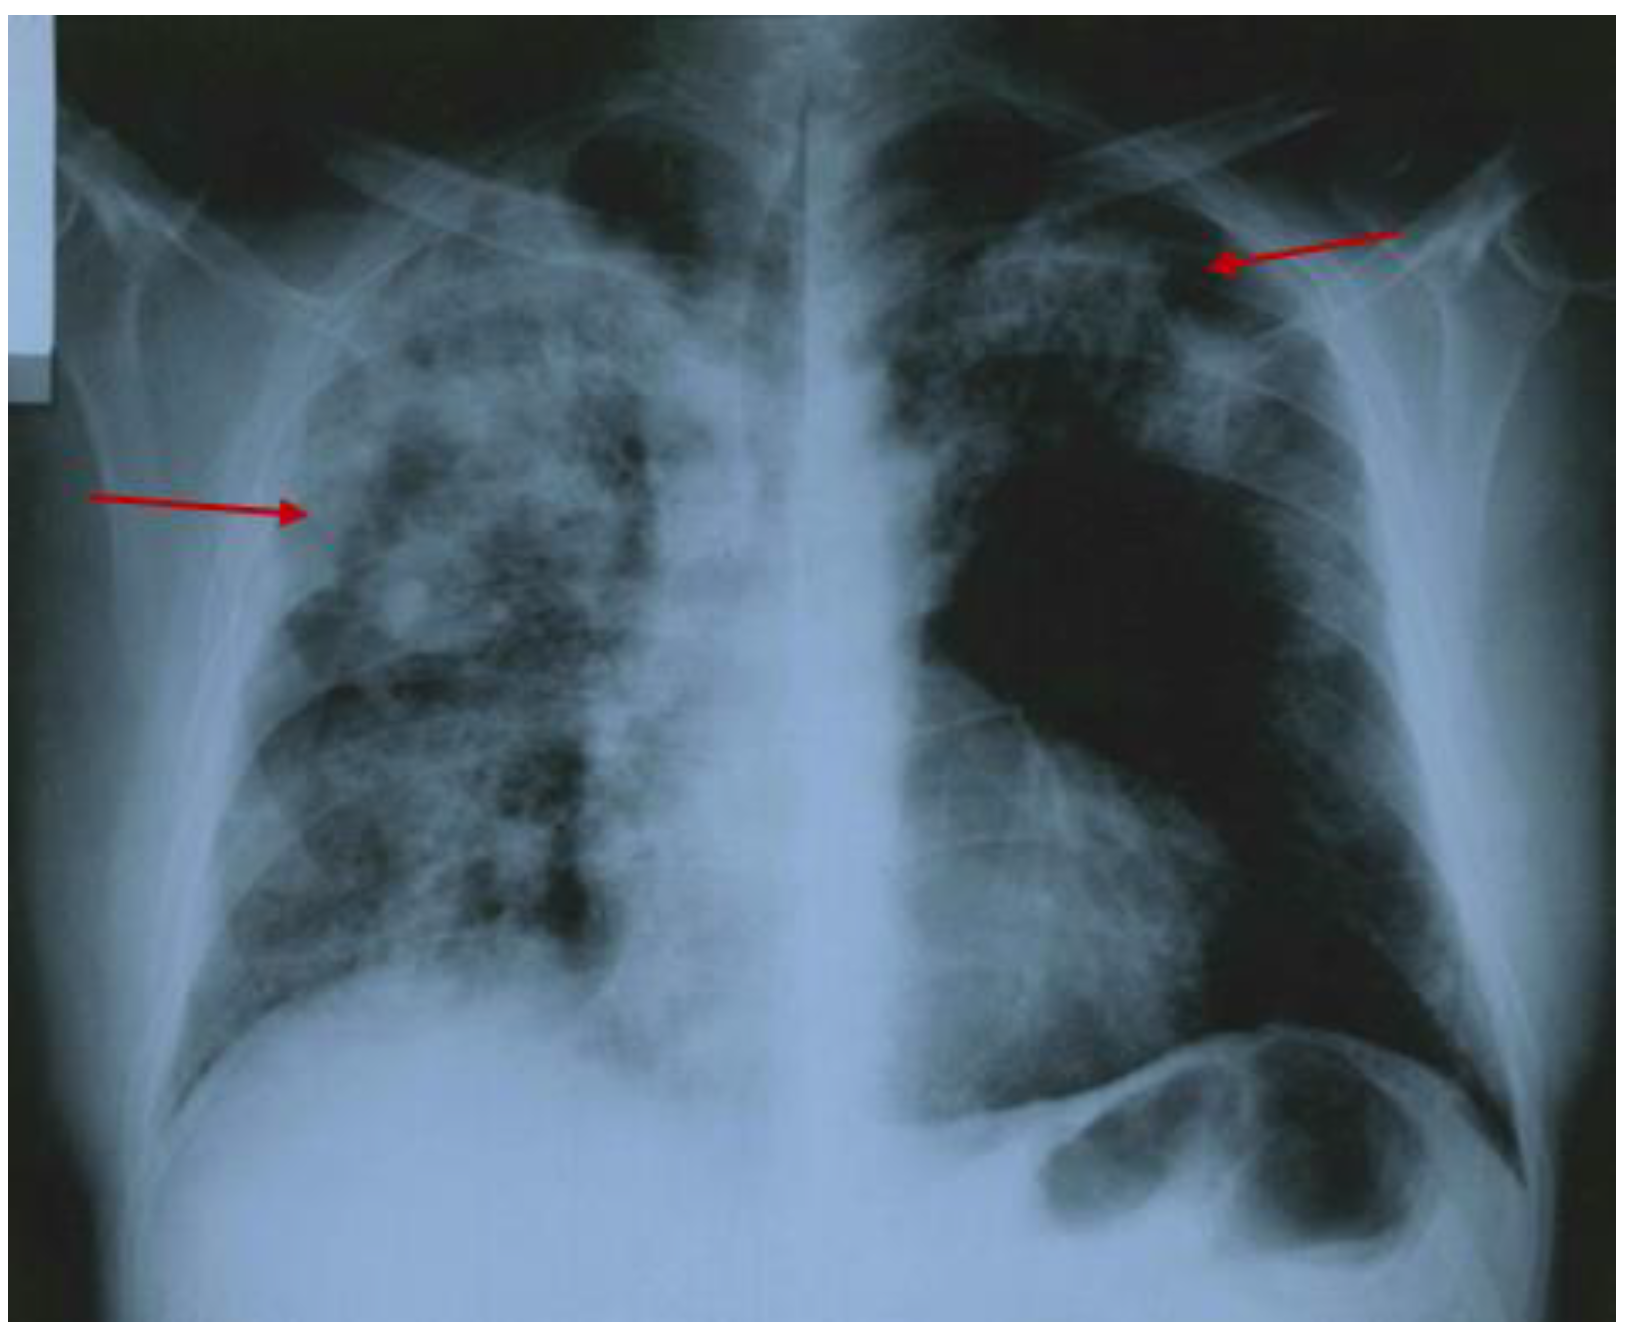

3.2.2. Additional Imaging Assessments